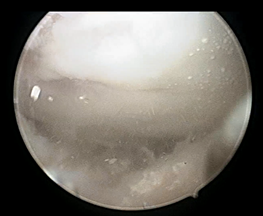

病例一:患者中年男性,左膝关节疼痛不适2年余。术前查血尿酸620umol/L,术前MRI和CT检查均未见明显异常。在行关节镜手术中,见大量痛风结晶沉积在软骨、韧带、半月板、滑膜表面!

使用刮匙清理关节痛风结晶: